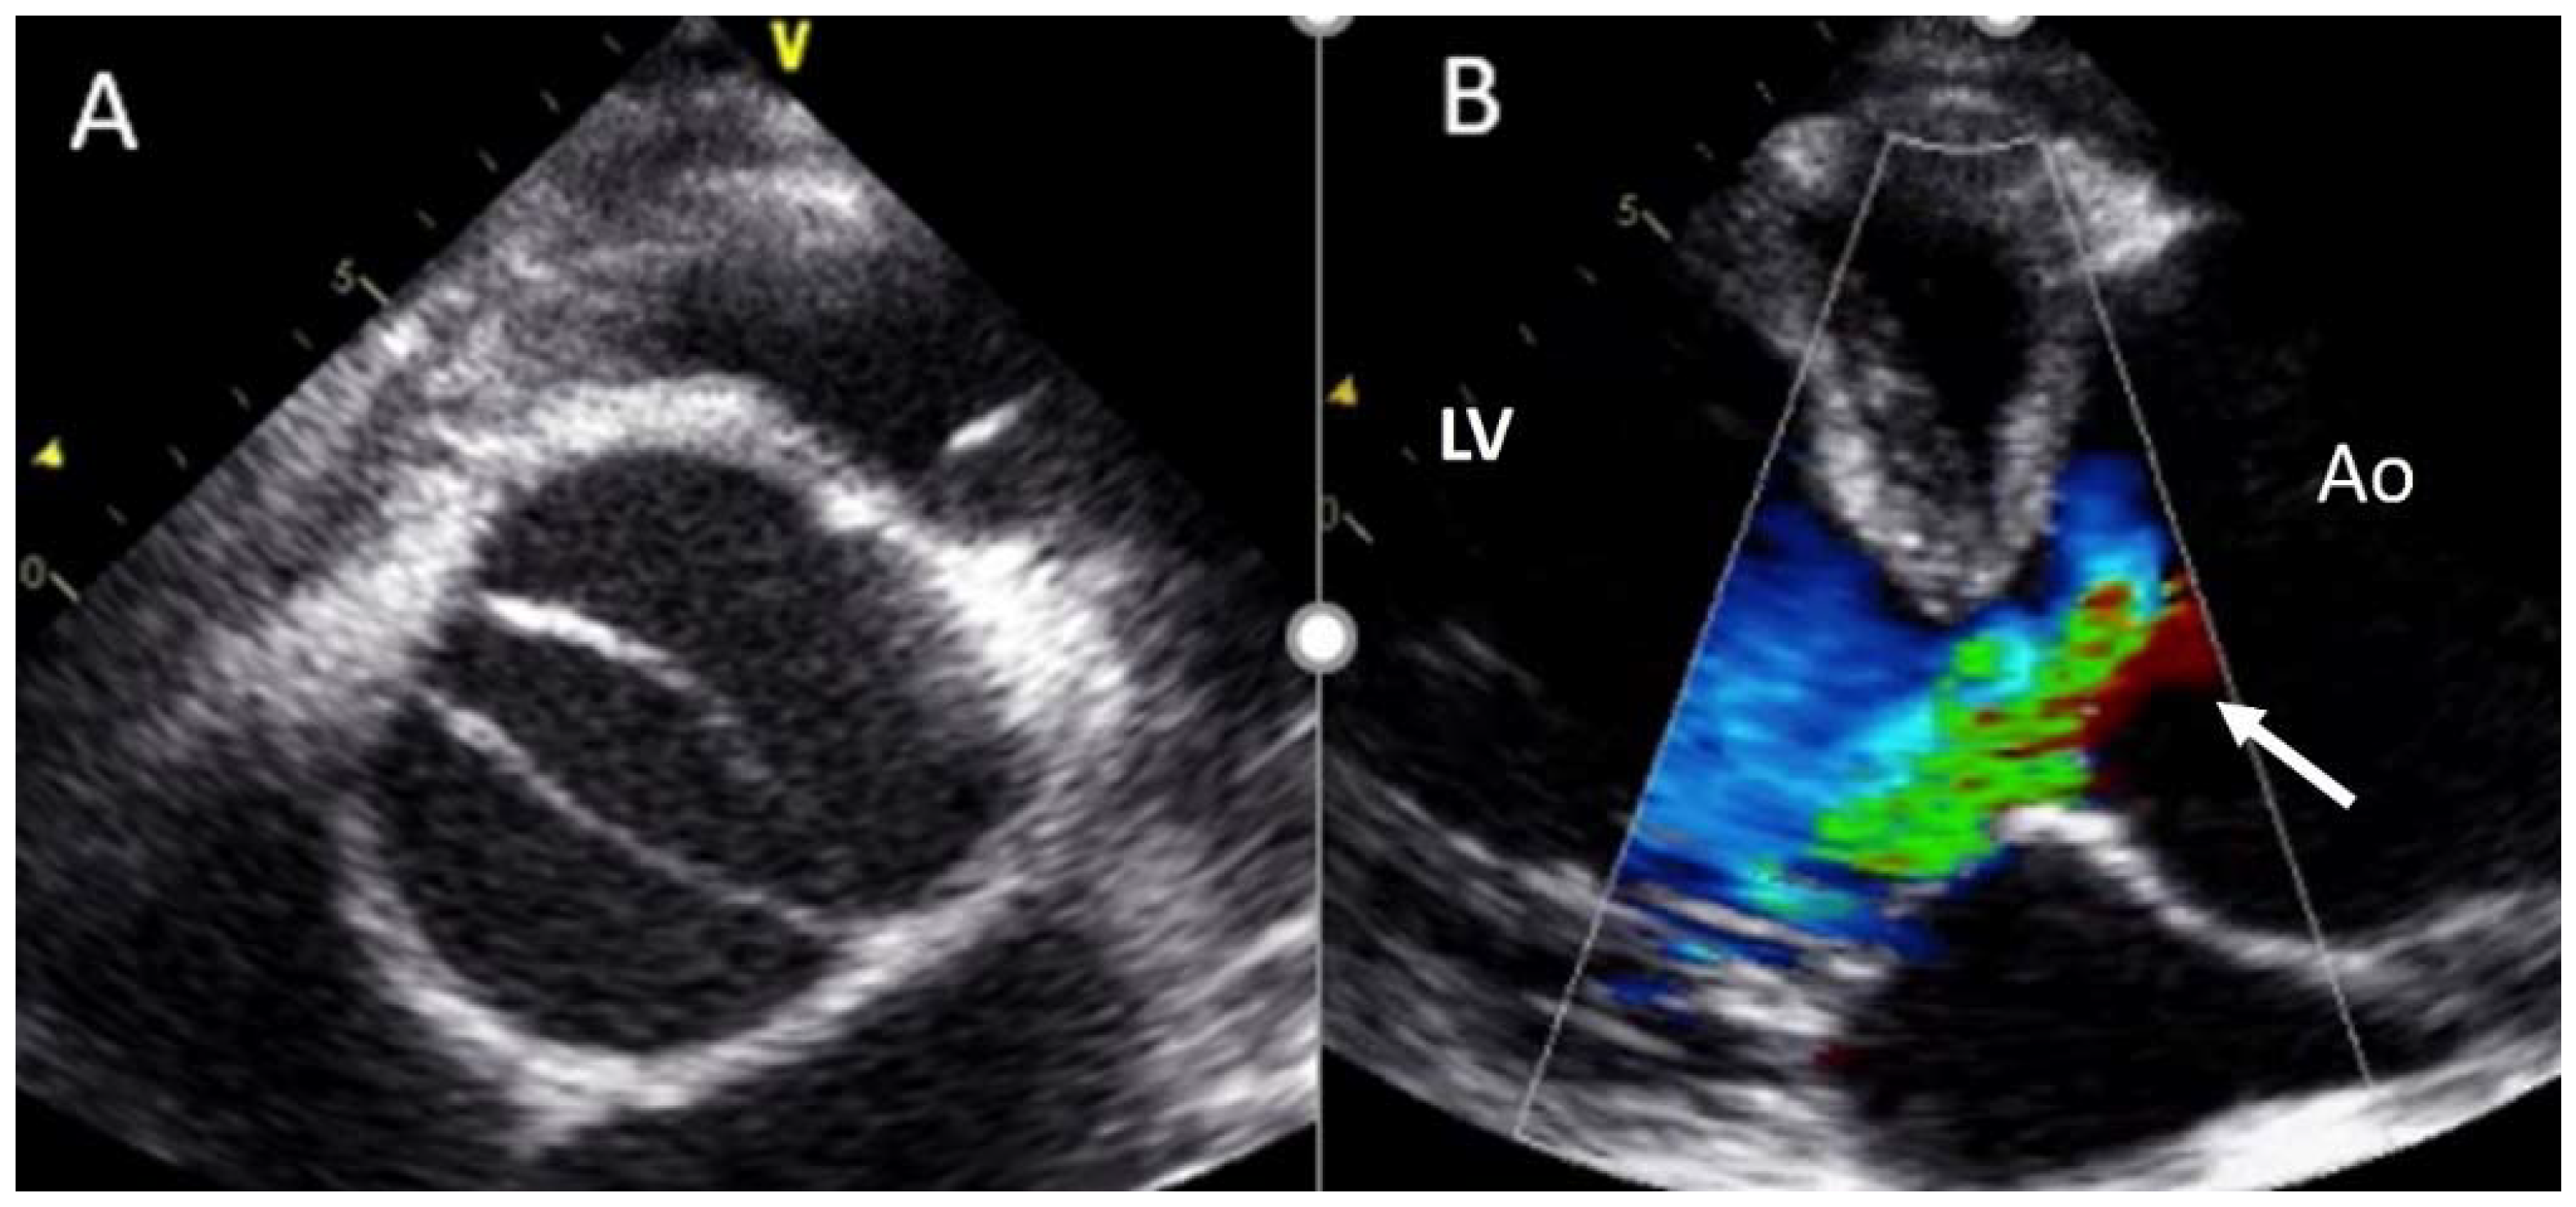

4.3. Aortic Regurgitation

- Myerson, S.G.; d’Arcy, J.; Mohiaddin, R.; Greenwood, J.P.; Karamitsos, T.D.; Francis, J.M.; Banning, A.P.; Christiansen, J.P.; Neubauer, S. Aortic regurgitation quantification using cardiovascular magnetic resonance: Association with clinical outcome. Circulation 2012, 126, 1452–1460. [Google Scholar] [CrossRef]

- Kammerlander, A.A.; Wiesinger, M.; Duca, F.; Aschauer, S.; Binder, C.; Zotter Tufaro, C.; Nitsche, C.; Badre-Eslam, R.; Schönbauer, R.; Bartko, P.; et al. Diagnostic and Prognostic Utility of Cardiac Magnetic Resonance Imaging in Aortic Regurgitation. JACC Cardiovasc. Imaging 2019, 12, 1474–1483. [Google Scholar] [CrossRef]

- Spampinato, R.A.; Jahnke, C.; Paetsch, I.; Hilbert, S.; Löbe, S.; Lindemann, F.; Strotdrees, E.; Hindricks, G.; Borger, M.A. Grading of aortic regurgitation by cardiovascular magnetic resonance and pulsed Doppler of the left subclavian artery: Harmonizing grading scales between imaging modalities. Int. J. Cardiovasc. Imaging 2020, 36, 1517–1526. [Google Scholar] [CrossRef]